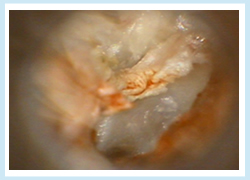

真珠腫性中耳炎

中耳炎という名がついていますが、事実上は腫瘍と同じような症状の進行をみせます。悪化すれば中耳周囲の組織を破壊し、場合によっては頭蓋内合併症を起こし、生命に危害を及ぼす可能性もある、危険な中耳炎です。